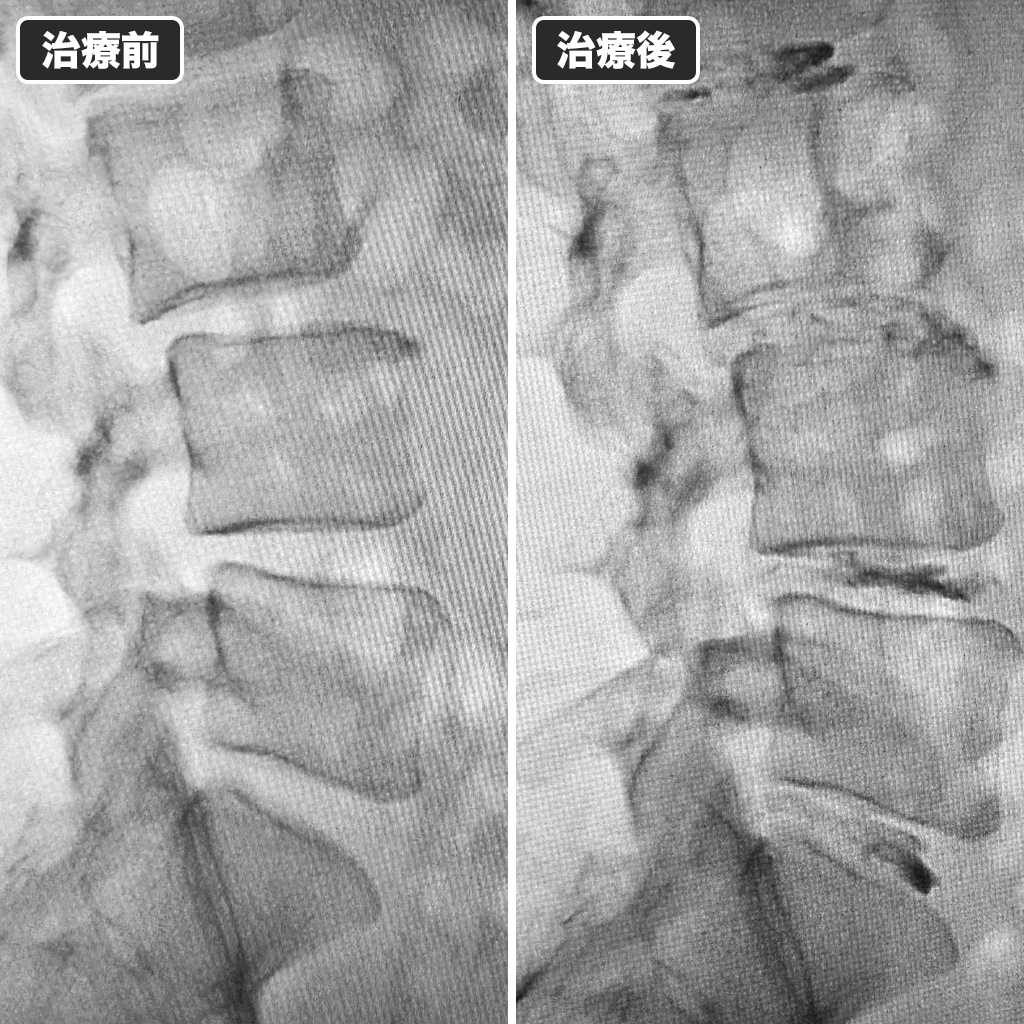

治療前後のレントゲン写真

治療前後のレントゲン写真になります。左側が治療前、右側が治療後になります。今年もあっという間の1年でした。たくさんのご紹介ありがとうございました。